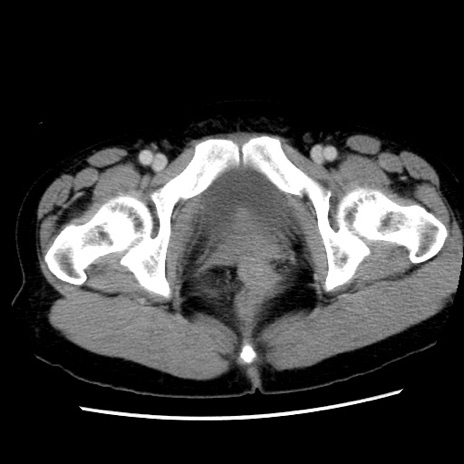

症例10(横断像)

【症例】 50歳代女性

【主訴】 腹痛

【現病歴】前日生レバーを食べた。今朝に排便あり。 昼前に突然発症の腹痛を生じ、当院救急外来を受診した。

【既往歴】 子宮筋腫にてで子宮全摘後

【身体所見】 意識清明、腹部:平坦、軟、下腹部やや左を中心に圧痛・反跳痛あり、筋性防御あり

【データ】WBC 7800、CRP 0.07